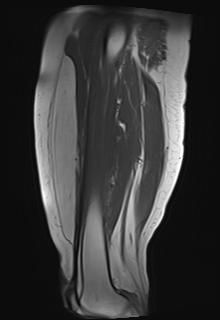

Intra-muscular lipoma